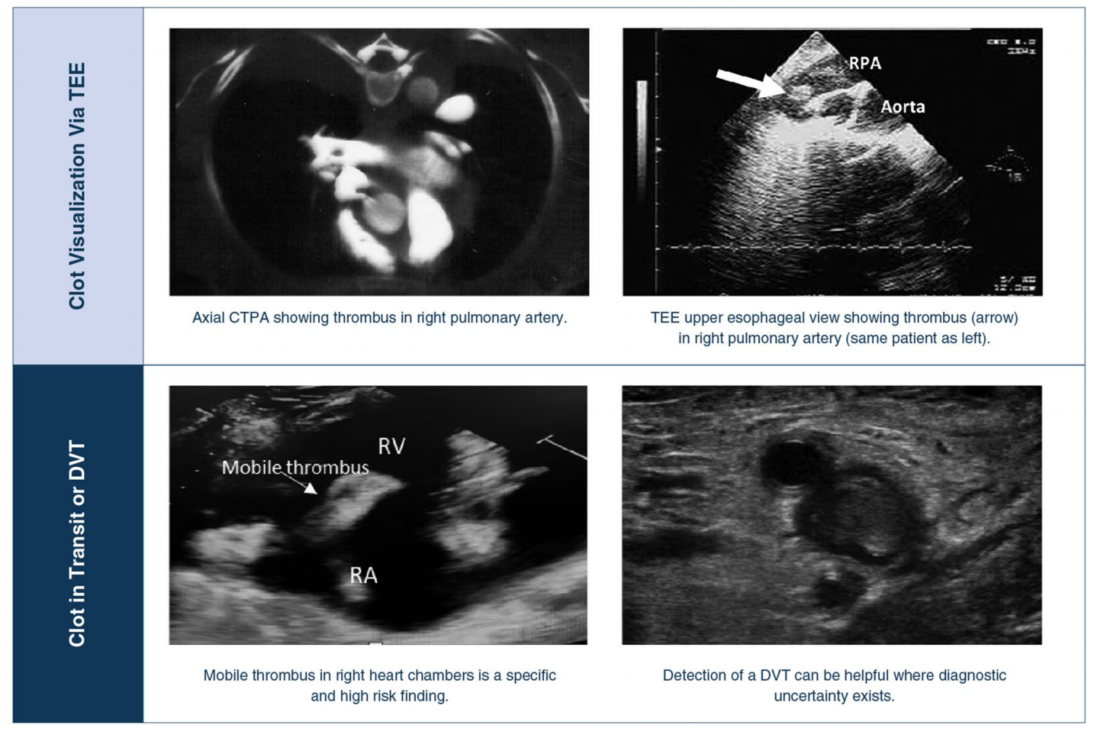

对于病情稳定的患者,除非能直接看到血栓,否则床旁超声心动图无法明确排除或排除 PE,这是因为 RVD 的非特异性和有限的阴性预测值。然而,在正确的临床背景下,特定的超声心动图异常有助于增加或减少 PE 的可能性,如果患者病情恶化且身体不适,无法进行 CTPA(图 1),超声心动图还可用于证明 PE 经验性治疗的合理性。深静脉血栓的检测对增加 PE 的可能性也有价值。经食道超声心动图(TEE)有时可通过观察主肺动脉或右肺动脉或右心房和/或心室中的血栓(血块在移动中)来确诊(图 2)。未进行有创通气的急性不适患者不应进行 TEE。重症监护医师应认识到,孤立的 RV 扩张在心脏骤停和恢复自主循环后很常见,在危重病人中也很常见,而且这一结果并非 PE 的特异性表现。

图 2 通过 CTPA、TEE、TTE 和 CCUS 观察血栓。AA 升主动脉,CCUS 重症监护超声,CTPA 计算机断层扫描,TEE,TTE 和 CCUS。肺血管造影,DVT 深静脉血栓。PA 肺动脉,SVC 上腔静脉,TEE 经食道超声心动图,TTE 经胸超声心动图、CCUS 重症监护超声